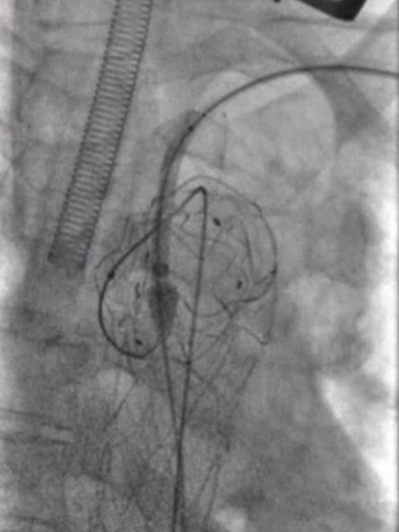

穿刺右股总动脉和左侧肱动脉,送入两根金标猪尾行主动脉造影,对各个径线进行精确测量。右前斜造影清晰显示假性动脉瘤的位置以及深度,为后续的手术操作提供了重要的参考依据。

★ 支架选择与释放

根据术前CT和造影的测量结果,选择PTBS3430180的锥形覆膜支架。在充分降压后,将覆膜区的近端定位在无名动脉后方,逐步释放覆膜支架。释放三节后,再次造影确认覆膜区位置定位良好,随后完成覆膜区全程释放,确保支架位置准确,为后续操作奠定基础。

★ 左侧颈总动脉重建

从预先切开好的左侧颈总动脉穿刺送入6f动脉鞘,将鞘头顶在覆膜支架上,使用asahi treasure 12导丝顺利突破覆膜区。

图1